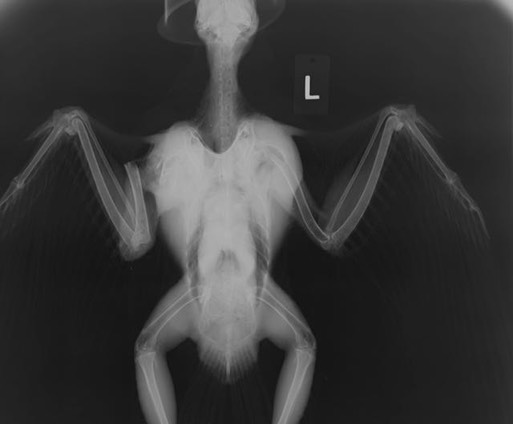

Peregrine Falcon 17-678

Peregrines can dive at speeds in excess of 200 miles per hour. We don’t know how fast this adult female was going when she hit a power line, but it must have been very fast. She fractured her right humerus and damaged the shoulder, elbow and wrist.